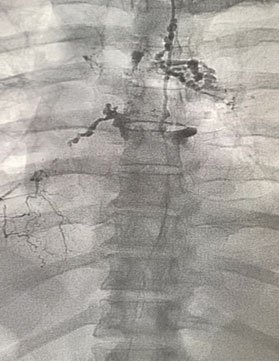

A type of x-ray machine, called a fluoroscope, projects the images on a TV monitor. The provider uses the images to follow the dye as it spreads through the lymphatic system up your legs, groin, and along the back of the abdominal cavity to identify the site of lymphatic leak. Then, embolizing agent (blocking agent) is used to block the site of leak.

Lymphangiography showing leak